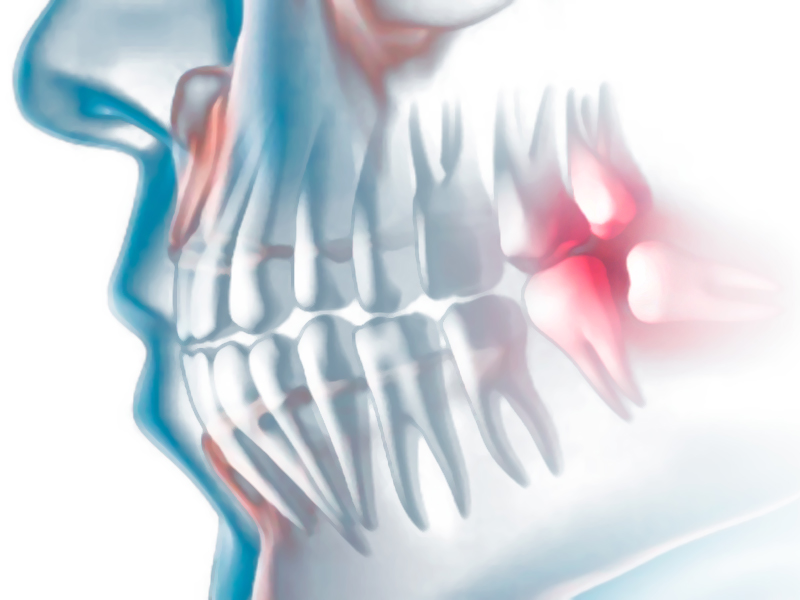

Realizamos otras intervenciones tales como: